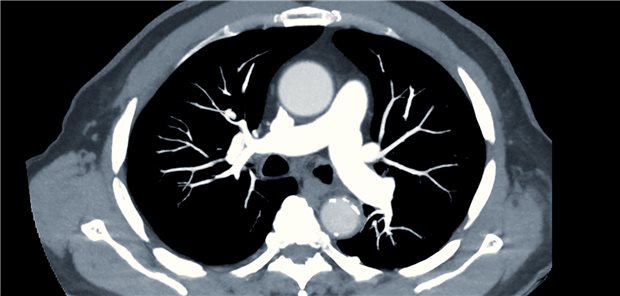

Bei einer schweren Lungenembolie geben viele Pneumologinnen und Pneumologen trotz immer ausgefeilterer Katheter-Technologien weiterhin der systemischen Thrombolyse mit Tissue Plasminogen Activator den Vorrang.